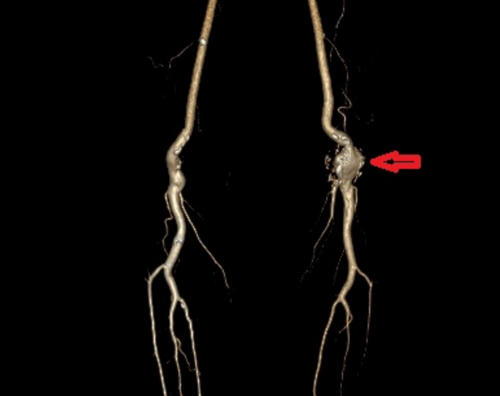

入院后,外周血管介入科主任、主任医师赵扬程详细询问了患者病史并为其进行了全面的体格检查,发现该腘动脉瘤位于左膝盖后方的腘窝处,大小约5 CM×4CM,摸之搏动明显。赵扬程解释,腘动脉位于人体腘窝内,负责向小腿及足部输送血液,腘动脉瘤是由于腘动脉血管壁发生异常扩张,从而形成囊状、球形的病变,并非真正的肿瘤。腘动脉瘤的发病原因尚未清楚,可能由吸烟、外伤、炎症等因素导致血管壁薄弱,动脉在血压的冲击下缓慢发生扩张,从而引起腘动脉瘤。

“该患者患有免疫风湿性疾病多年,手脚多处关节出现变形,腘动脉也存在不同程度的损伤,由此发展形成了腘动脉瘤。”赵扬程表示,当前患者的左侧腘窝处动脉瘤压力过大,破裂出血,致使局部形成的血栓阻塞下肢血流灌注,加上血栓的脱落随时可造成左下肢分支动脉的栓塞,将会严重影响其下肢血供,使患者无法日常活动,更严重的情况是还可造成下肢肌肉组织坏死,有截肢的风险。

由于瘤体正好处于膝关节后,介入手术放置支架容易造成支架移位和折断,患者更适合通过血管外科手术方式达到切除动脉瘤和清除瘤腔中的血栓。赵扬程立刻执行多学科协作诊疗方案,邀请副院长、手足显微外科专家、主任医师刘鸣江,风湿免疫科罗徐医师讨论患者的手术方案。刘鸣江院长结合患者影像学检查,详细询问患者病情,仔细检查患者双下肢动脉搏动,浅表静脉走形,腘动脉瘤病灶等情况,同时考虑到患者体型偏瘦,双下肢浅表静脉细的特点,最终确定最优手术方案。

1月30日,刘鸣江副院长与创伤骨科、手足显微外科副主任医师李亮,外周血管介入科主治医师邓江北等多名专家为吴建国行左侧腘动脉瘤切除、腘动脉切开取栓、自体动脉断端吻合术,顺利摘除动脉瘤。吴建国术后恢复良好,他对于医疗团队帮他摘掉了左膝盖窝这颗折腾他近一年的“炸弹”,表示由衷的感谢。